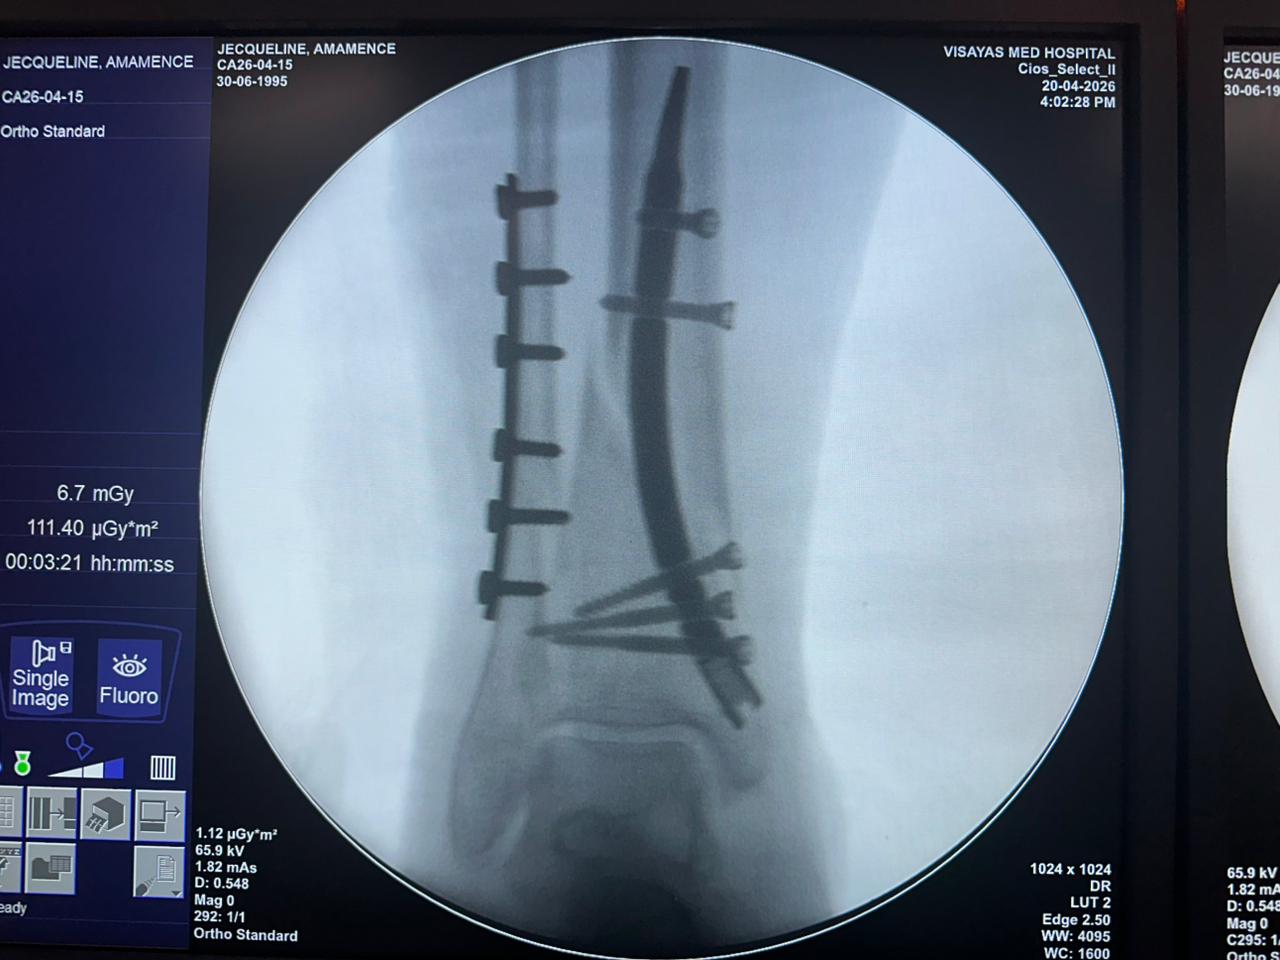

Distal Tibial Nail Fixation Case Study with Fibular Plate Support

Patient:

31-year-old patient

Surgical Area:

Distal tibia and fibula

Product Used:

Distal Tibial Nail

Fibular Locking Plate

Imaging:

Intraoperative C-arm fluoroscopy, AP and lateral views

Case Summary:

This case involved distal tibial fixation using an intramedullary distal tibial nail. Intraoperative fluoroscopy confirmed the position of the nail, distal locking screws, and fibular plate fixatio